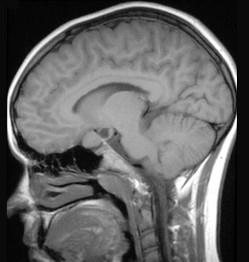

问题 关于星形细胞瘤(如图所示)的描述错误的是()

选项 A.肿瘤多呈浸润性生长 B.可分为纤维型、原浆型、肥胖细胞型 C.主要位于灰质内 D.实性者无明显边界 E.可不限于一个脑叶

答案 C